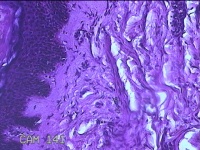

左前臂结节

性别

女

年龄

46岁

临床诊断

皮脂腺囊肿

发现左前臂结节4个月余,无明显疼痛及不适。

标本名称

大体所见

灰白暗红色组织1.3x0.8x0.3cm一块,表面带梭形皮肤1.2x0.3cm,皮下见结节1x0.8x0.3cm一个,切开结节呈实性,切面灰白粉红色,质软。